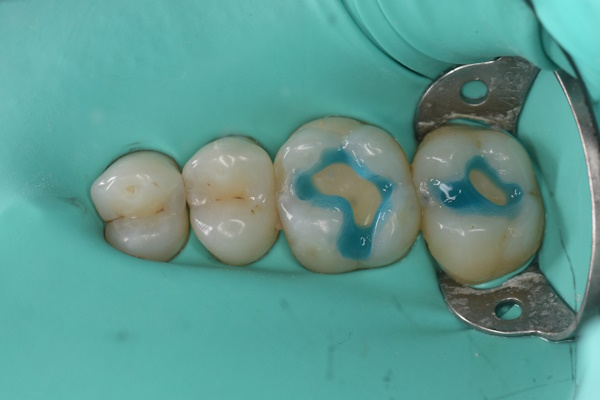

セラミック治療の治療例です。奥歯の虫歯を、見た目もきれいな材料で治したいとのご希望で来院されました。当院にて、2本同時にセラミック治療を行いました。接着効率を高めるため、ラバーダムを使用しています。オキシガードは、過酸化物と還元剤による化学重合反応により、歯科接着用レジンセメント表面の未重合層を硬化させる材料です。さらに、未重合層を空気から遮断することで、確実な硬化を促します。

術前から術後までの治療の流れ

エッチング後